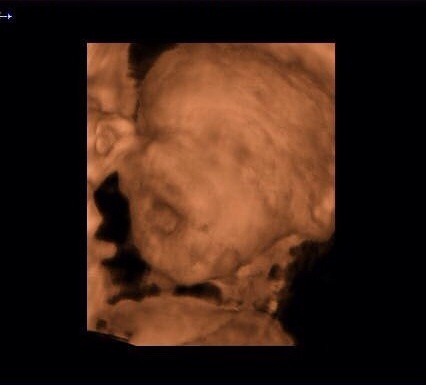

When I had my NT scan and A/S done they flipped on the 3d/4d for a little while to take a look, you could make out LO's face pretty decently at 21 weeks, so I'd say anytime after that and before things start getting cramped at around 30+ weeks should be good. I wouldn't worry about the safety part. There's no good evidence that ultrasounds pose any risk to unborn fetuses, and in many countries women are given routine ultrasounds at every visit and have no ill effects. Your doctor is just trying to cover their ass.

Personally, not a fan of the 3d/4d pictures and don't see the point unless medically indicated. I've seen a lot of them and I think most babies don't look that different and just find the 2d pictures to be cuter. If you're wondering on timing, I'd guess whichever boutique you're looking into will have some recommendations on timing and I'd probably go with whatever they say.

Also I love the 3D because all my 2D look like alien babies and this one actually looks like a human baby